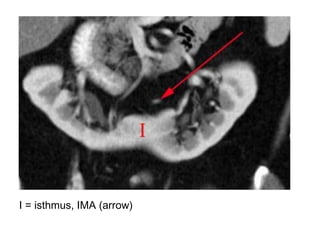

Horseshoe kidney with anteriorly oriented renal pelvis, axial contrast-

enhanced MDCT image (a) shows a horseshoe, the renal isthmus is

volume rendering (b) better show the inferior renal isthmus, the

normal renal arteries, and the anterior location of the renal pelvises

I = isthmus, IMA (arrow)